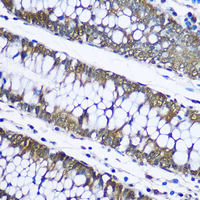

Immunohistochemical analysis of UBB staining in human colon formalin fixed paraffin embedded tissue section. The section was pre-treated using heat mediated antigen retrieval with sodium citrate buffer (pH 6.0). The section was then incubated with the antibody at room temperature and detected using an HRP conjugated compact polymer system. DAB was used as the chromogen. The section was then counterstained with haematoxylin and mounted with DPX.